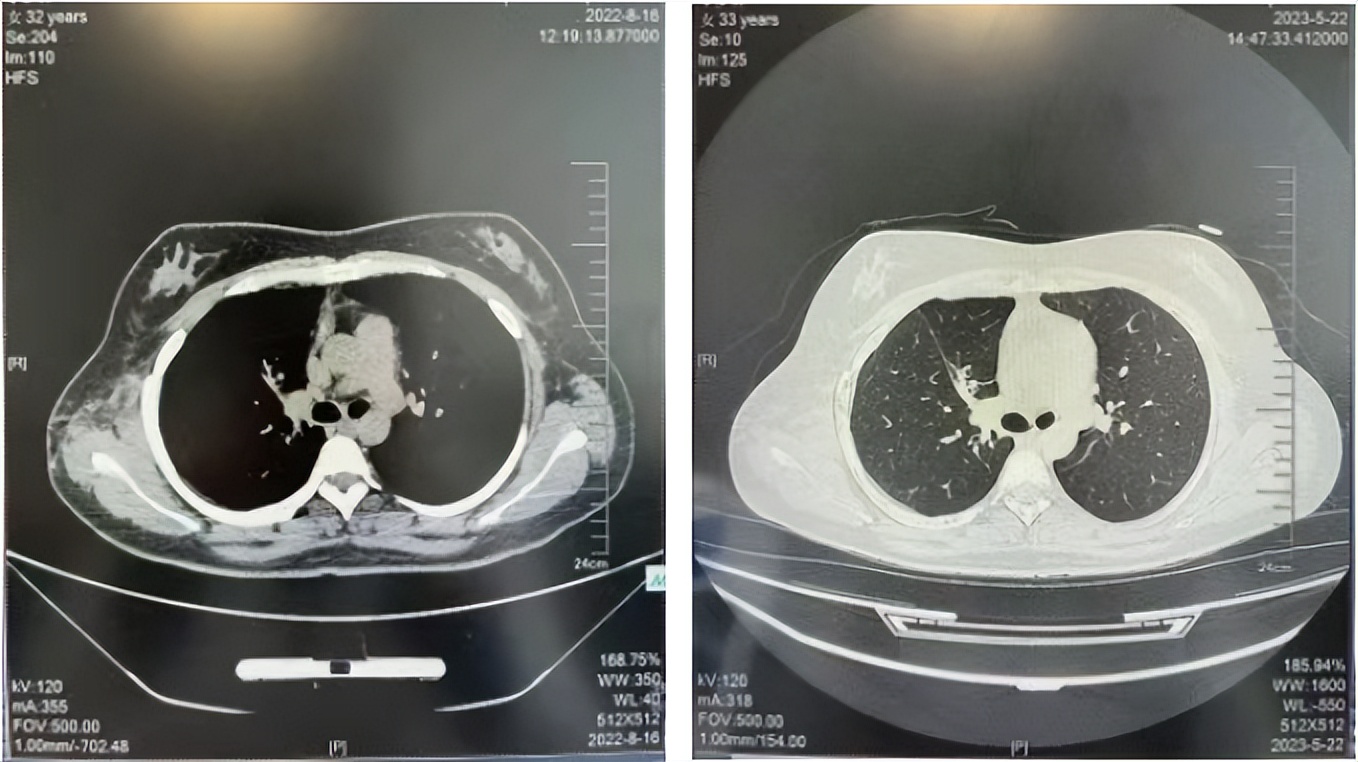

2016年1月复查CT提示支气管截断可见新发小结节,一线治疗采用培美曲塞+DDP方案化疗4周期(培美曲塞3.36,DDP 480mg)。化疗后复查胸部CT:右肺见不规则结节样影,最大层面大小约19mm*8mm,较前比较明显增大,疗效评估PD。2017.3-2017.4予单药多西他赛化疗3周期,疗效评估SD。2018年5月末复查CT提示结节较前增大,评效为PD,2018年6-10月予多西他赛+CBP化疗4周期,疗效评估SD。2022年5月患者出现活动后气短,复查胸部CT示右肺膨胀不良;右侧胸腔积液增多。胸腔积液包埋病理示符合肺腺癌细胞。行NGS基因检测:EML4:exon13-ALK:exon20融合。PD-L1(克隆号22C3)TPS<1%。

临床诊断:右肺上叶恶性肿瘤rT0N0M1a IVA期(第9版分期);恶性胸腔积液。

诊疗经过:2022年5月始口服克唑替尼3个月,出现肝功能异常(DILI 2级伴临床症状),改用恩沙替尼靶向治疗至今,目前评效为维持PR。恩沙替尼应用期间出现轻度肝功能异常(DILI 1级),对症处理后好转。截止目前PFS 33个月。

2022.08

2023.05